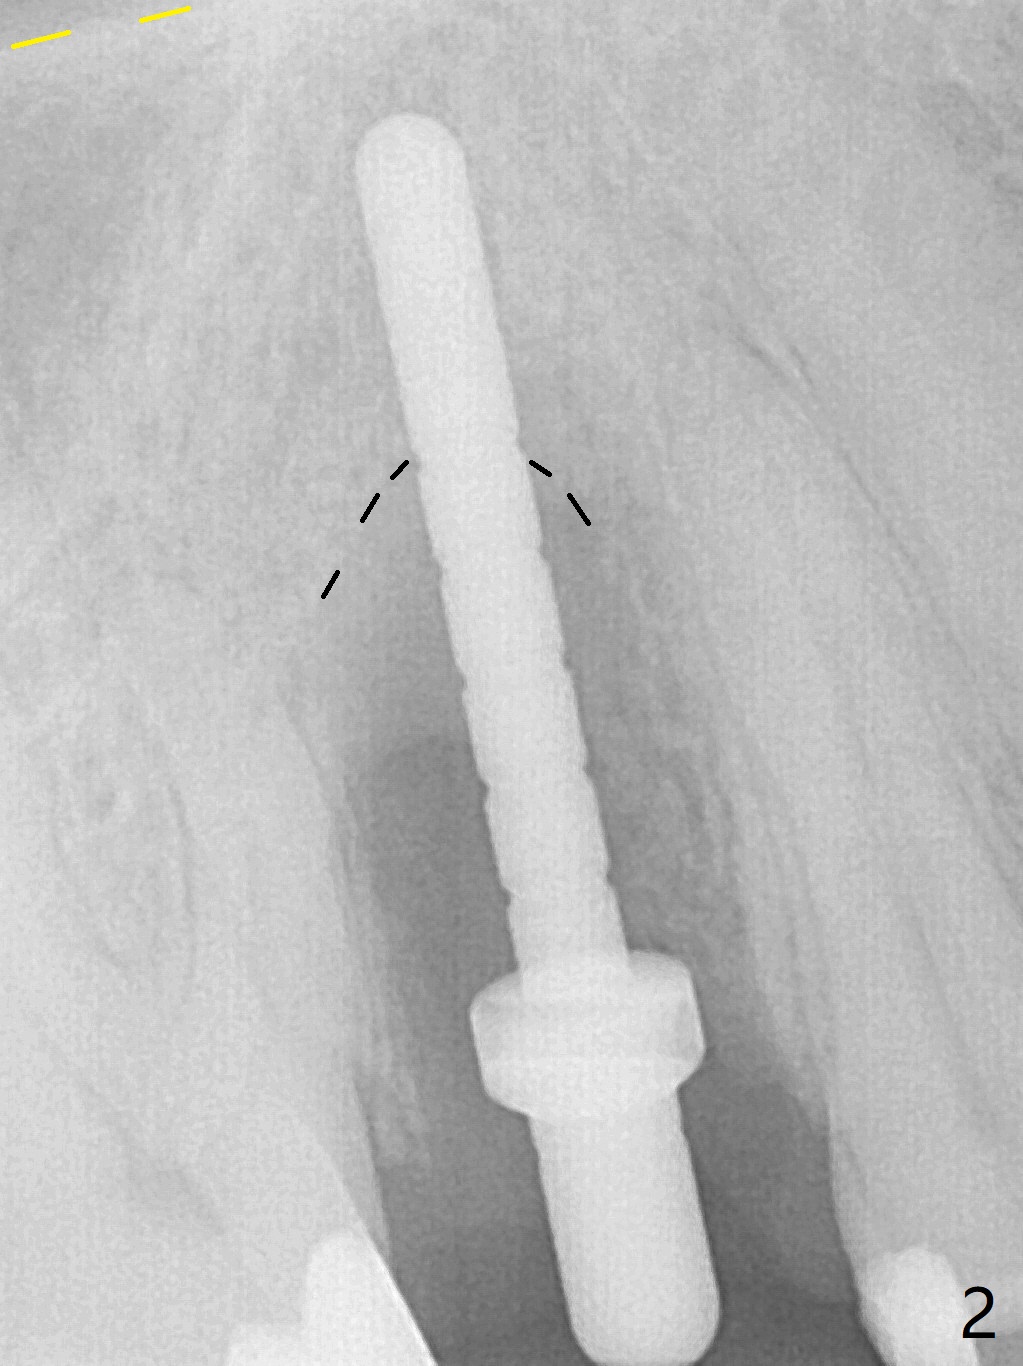

When the tooth #4 with vertical root fracture (Fig.1) is extracted, the buccal plate is found to be lost. The lowest point of the defect is shown as black dashed line in Fig.2 (yellow dashed line: sinus floor). After use of 2.5 mm reamer for 21 mm (buccal gingival level) and 3.0 mm reamer for ~17 mm, a 3.8x15 mm dummy implant is placed with 30 Ncm and 1.85 mm apical space (Fig.3 pink outline). A 3.8x18 mm (definitive) implant is placed with <40 Ncm with the implant plateau apical to the lingual crest (Fig.4,5). The buccal plate defect is repaired by Vanilla Graft (Fig.6 *) before and after insertion of a 4.5x4(3) mm abutment. The buccal plate defect seems to being repaired 4 months postop (Fig.7). Occlusal wear suggests bruxism, which is also associated with the root fracture. Night guard is recommended. The defect repair is close to completion 8 months post cementation (Fig.8). The crown/abutment is found to be loose 1 year 4 months post cementation and retightened without checking whether there is clinical 2nd DO caries of #3 (Fig.9, "sensitive to water pik"). A few days later, DO composite is being removed. It is difficult to determine whether the 2nd DO caries or gap has been removed with the neighboring crown in place. When the crown/abutment is removed and gingival retractions are inserted, there is no decay. The gap is removed. With Toflemire in place, the crown/abutment is reseated and hand tightened; after packable composite, the crown/abutment is removed, there is no more DO gap.